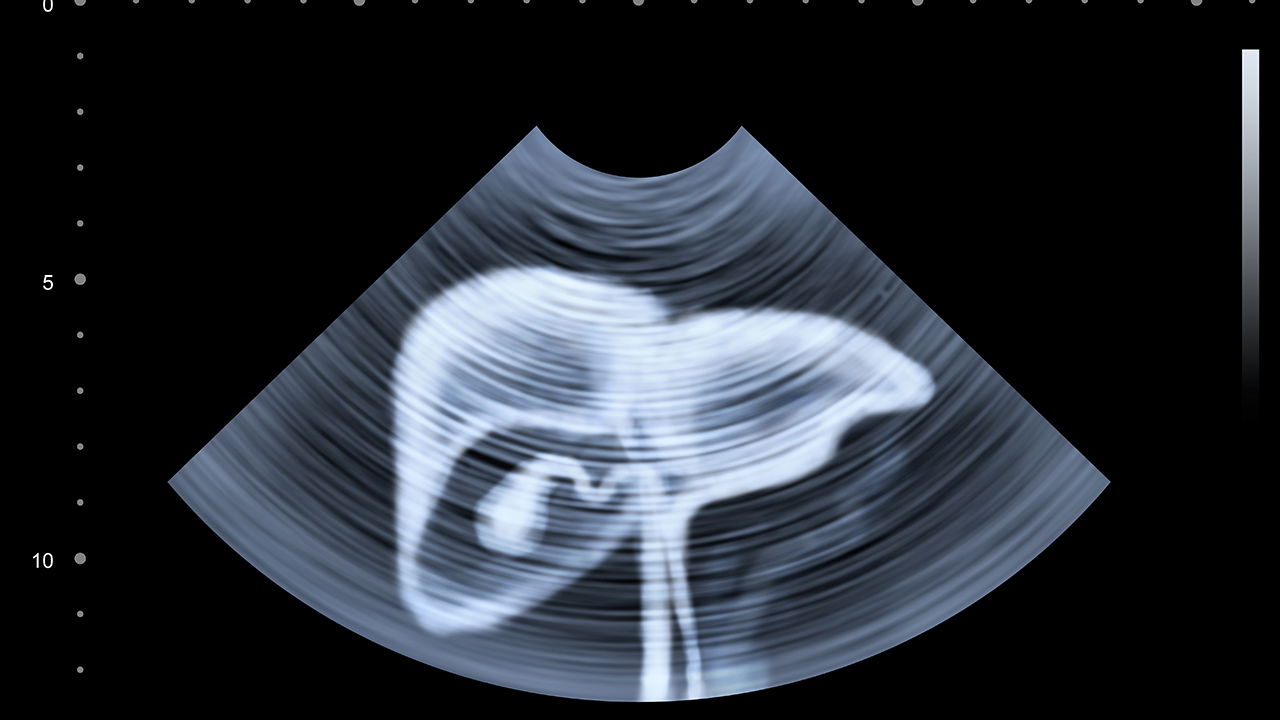

肝癌的预防与健康管理至关重要。乙肝、丙肝病毒感染是肝癌的主要诱因,接种乙肝疫苗、定期体检可降低患病风险。肝硬化患者应每6个月进行超声和甲胎蛋白检查,以便早期发现肝癌。日常生活中应避免饮酒、减少高脂肪饮食,保持健康体重,规律作息,增强免疫力。肝癌患者术后需定期复查,遵医嘱服药,避免过度劳累,保持良好的心态有助于康复。